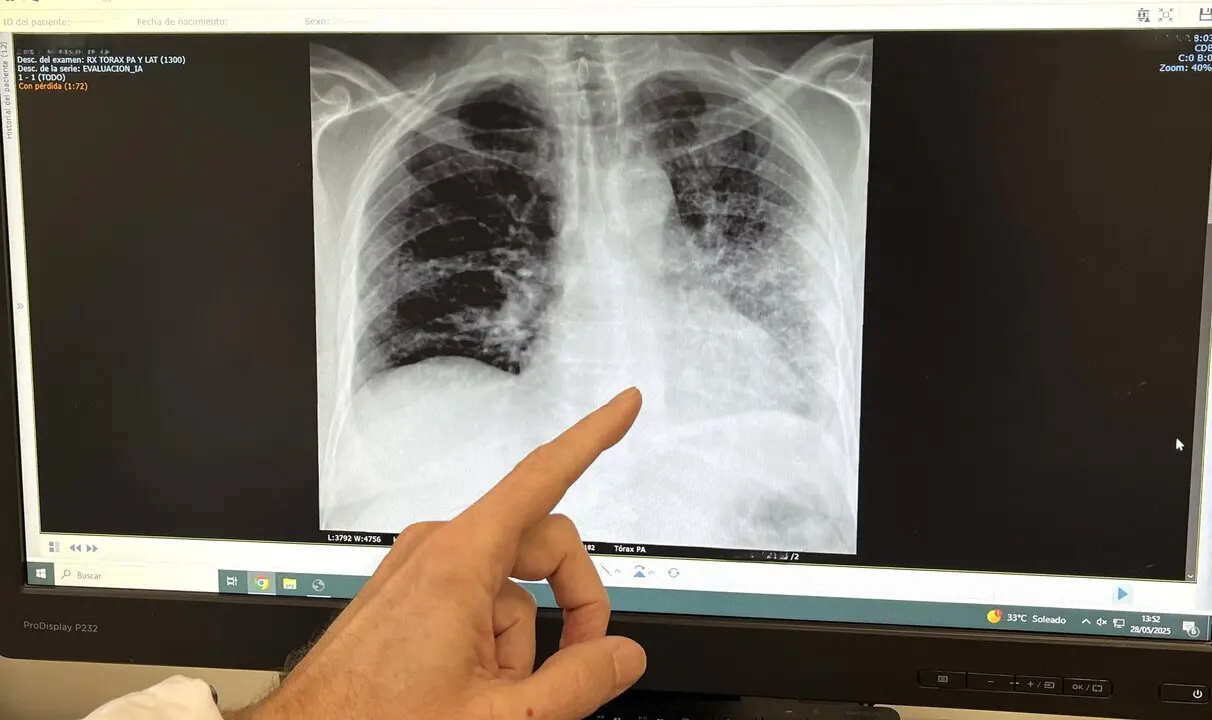

RX de paciente fumador con cáncer de pulmón

El tabaco es el responsable de más del 85% de los casos de cáncer de pulmón, así como de enfermedades como la Enfermedad Pulmonar Obstructiva Crónica (EPOC), bronquitis crónica y exacerbaciones del asma, según ha recalcado el doctor José Daniel Alcázar, jefe de servicio de Neumología del Hospital Quirónsalud Málaga. El doctor Alcázar ha afirmado que “en el Hospital Quirónsalud Málaga seguimos comprometidos con la prevención, el diagnóstico precoz y el tratamiento de enfermedades respiratorias vinculadas al tabaco”. Gracias a la incorporación reciente de la técnica EBUS (ecobroncoscopia), “damos un paso más en la detección y estadificación de enfermedades pulmonares, incluyendo el cáncer de pulmón, de forma mínimamente invasiva y con la máxima precisión diagnóstica”.